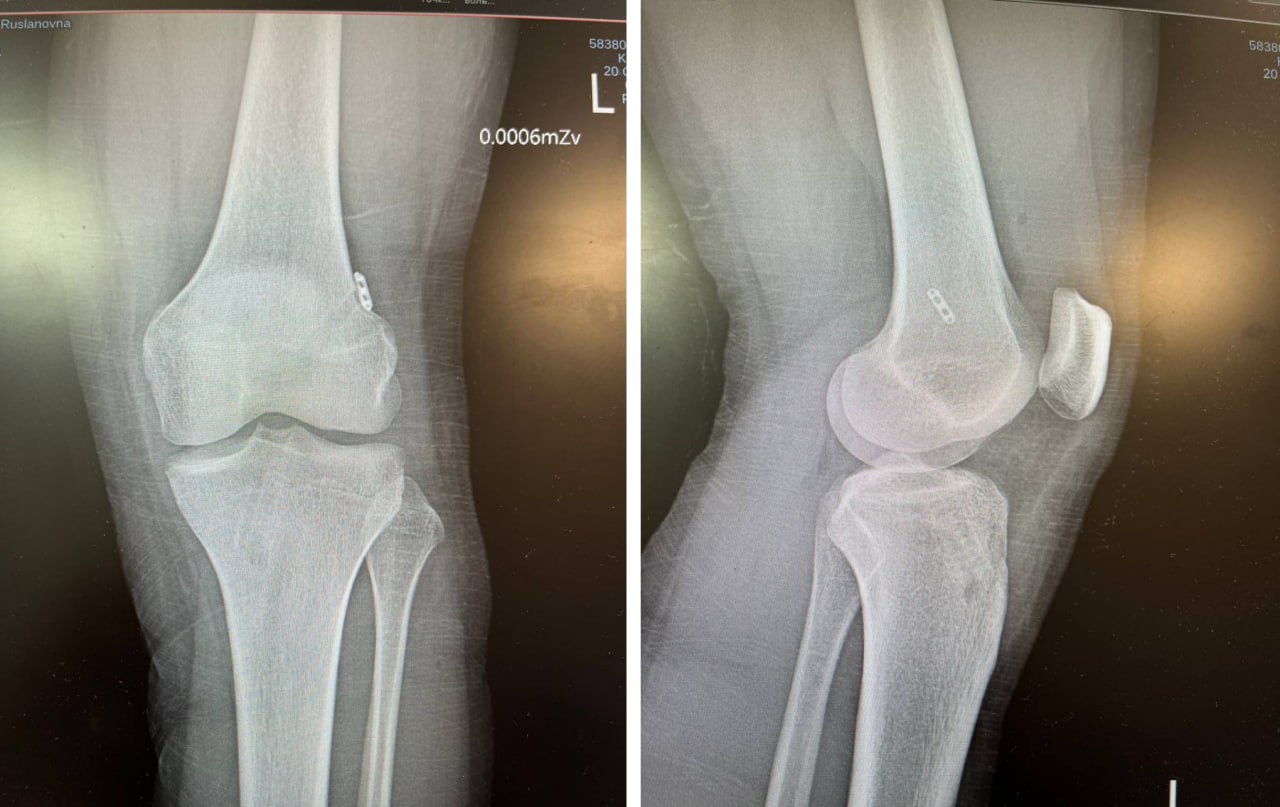

Спасение к ней пришло из Челябинска! Врачи ЧОКБ провели сложнейшую операцию, используя уникальную «прошивалку» для мениска, и помогли Софье не просто встать на ноги, но и вернуть в большой спорт.